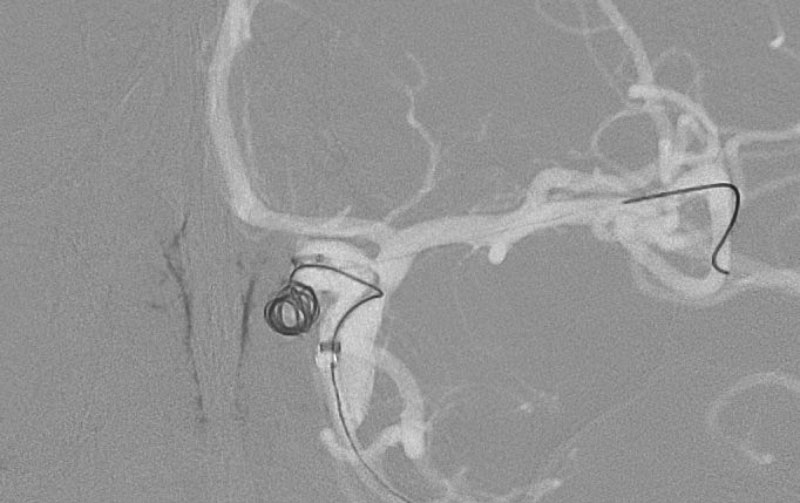

'25年10月

くも膜下出血

前交通動脈瘤破裂

40代

大阪府の病院

No.1589 手術前

No.1589 手術中

No.1589 手術後